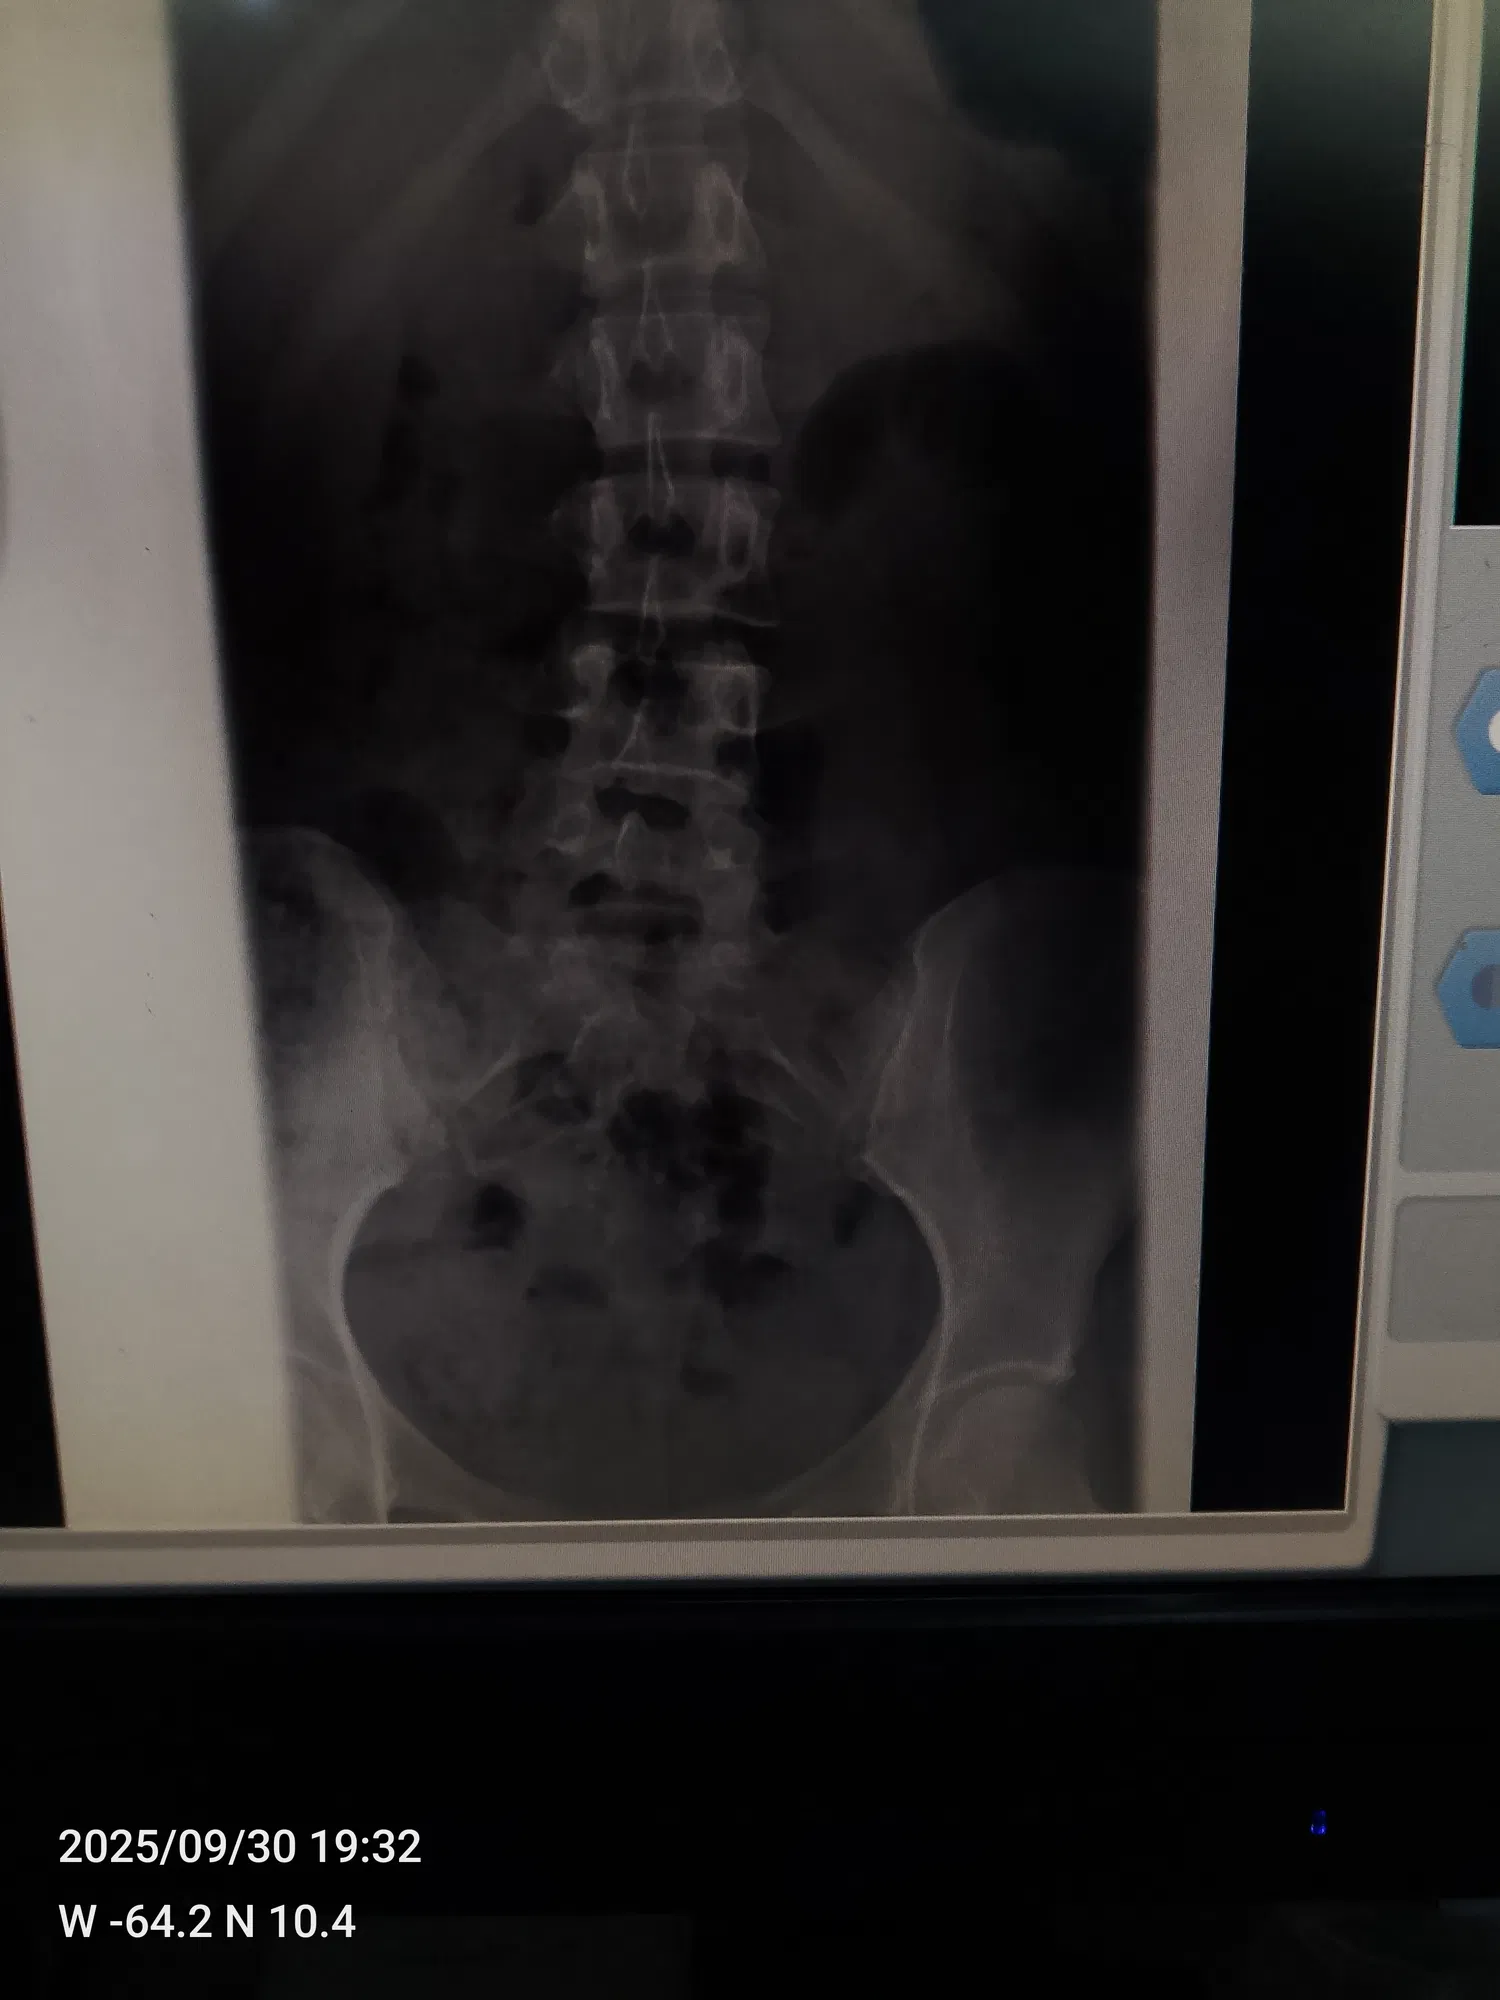

<liketuimages> <center>         </center> </liketuimages> ### Holaaa queridos amigos,¿cómo han estado? espero que hayan tenido un excelente fin de semana ❤️✨ he estado un poco perdida de por acá ya que me he estado sintiendo demasiado mal 😣 hace días les comenté que fui al traumatólogo ya que me había caido en dónde trabajo y me di un golpe súper fuerte en la columna ☹️ >Hello dear friends, how have you been? I hope you had a great weekend ❤️✨ I've been a little absent from here because I've been feeling really bad 😣 A few days ago, I told you that I went to the orthopedist because I fell at work and hit my spine really hard ☹️ ---- ### Desde que me caí no aguanto los dolores en la columna, coxis y cervical, del mismo golpe que me di tuve un derrame ( parecía el periodo pero eso no era ya que yo ya había visto periodo ese mes) mi mamá me llevo a el traumatólogo y la doctora me mando un tratamiento y reposo por una semana,en las placas que me hice antes de ir no salía nada malo.. >Since I fell, I can't stand the pain in my spine, tailbone, and neck. From the same blow, I had a hemorrhage (it looked like my period, but it wasn't because I had already had my period that month). My mom took me to the orthopedist, and the doctor prescribed treatment and rest for a week. The X-rays I had taken before going didn't show anything wrong. --- ### Cumplí mi reposo y me tomé el tratamiento que me mandó la doctora pero la verdad eso no me hizo efecto me sentía muy mal, las pastillas me calmaban el dolor un poco ya después el dolor volvió más fuerte ☹️ fui y me hice otras placas más y el radiólogo nos dijo que estaba teniendo una pequeña desviación y que se veía como una fisura que fuera a el traumatólogo a ver que era, mi mamá me llevo nuevamente para que la doctora y la misma dijo que no tenía nada y me mandó a tomar pregabalina y la verdad amigos me tomé una sola pastilla y me dió taquicardia sentía que me iba a morir me dió mucho miedo y no me la tomé más, mi mamá tuvo que buscarme la cita con otro traumatólogo, así que el día martes el doctor Luis Cova me va a ver.. >I rested and took the treatment prescribed by the doctor, but honestly, it didn't work. I felt terrible. The pills calmed the pain a little, but then the pain came back even stronger. ☹️ I went and had more X-rays taken, and the radiologist told us that I had a slight deviation and that it looked like a crack. He said I should go to the orthopedist to see what it was. My mom took me back to the doctor, and she said there was nothing wrong and prescribed pregabalin. To be honest, friends, I took just one pill and it gave me tachycardia. I felt like I was going to die. I was really scared and didn't take any more. My mom had to make an appointment with another orthopedist, so on Tuesday, Dr. Luis Cova is going to see me. --- ### Muchas personas ya nos han dicho que si tengo una desviación y algo más que obviamente lo va a ver el doctor, así que bueno esperaré hasta el martes Pero les digo amigos, ese dolor me hace llorar es demasiado fuerte 😭☹️ por eso he estado perdida de por acá,ya pronto volveré con mucho contenido para ustedes ❤️ síganme en mis redes de tiktok e Instagram por allá siempre subo algo ❤️ mi usuario de tiktok es @Fiorem17 y de Instagram es @Fiorem19 >Many people have already told us that if I have a deviation and something else that the doctor will obviously see, then I'll wait until Tuesday. But I tell you, friends, that pain makes me cry, it's too strong 😭☹️. That's why I've been missing from here. I'll be back soon with lots of content for you ❤️ Follow me on TikTok and Instagram, I always post something there ❤️ My TikTok username is @Fiorem17 and my Instagram is @Fiorem19 --- ### Acá les dejare algunas fotos que me he tomado jajaja y les quiero mostrar una torta que hice hoy en la mañana con ayuda de mi hermano ajajaja la hice en mi cuarto sentada en la cama así que fue un rato hacerla jajajaja y quedó linda, les dejare también las fotos de las placas por si algunos de ustedes es doctor las vea y me dice si ve algo malo por fa ☹️☹️☹️ >Here are some photos I took, hahaha, and I want to show you a cake I made this morning with my brother's help, hahaha. I made it in my room sitting on my bed, so it took a while, hahaha, but it turned out cute. I'll also leave you the photos of the X-rays in case any of you are doctors and can take a look and tell me if you see anything wrong, please ☹️☹️☹️ --- ##### <div class="pull-left"> - ### El texto es completamente de mi autoría. </div> ##### <div class="pull-right"> - ### The text is entirely by me. </div> --- ##### <div class="pull-left"> - ### Traducción realizada con DeepL Traslate. </div> ##### <div class="pull-right"> - ### Translation using DeepL Traslate. </div> --- For the best experience view this post on [Liketu](https://liketu.com/@fiorem17/un-nuevo-post-para-ustedes)